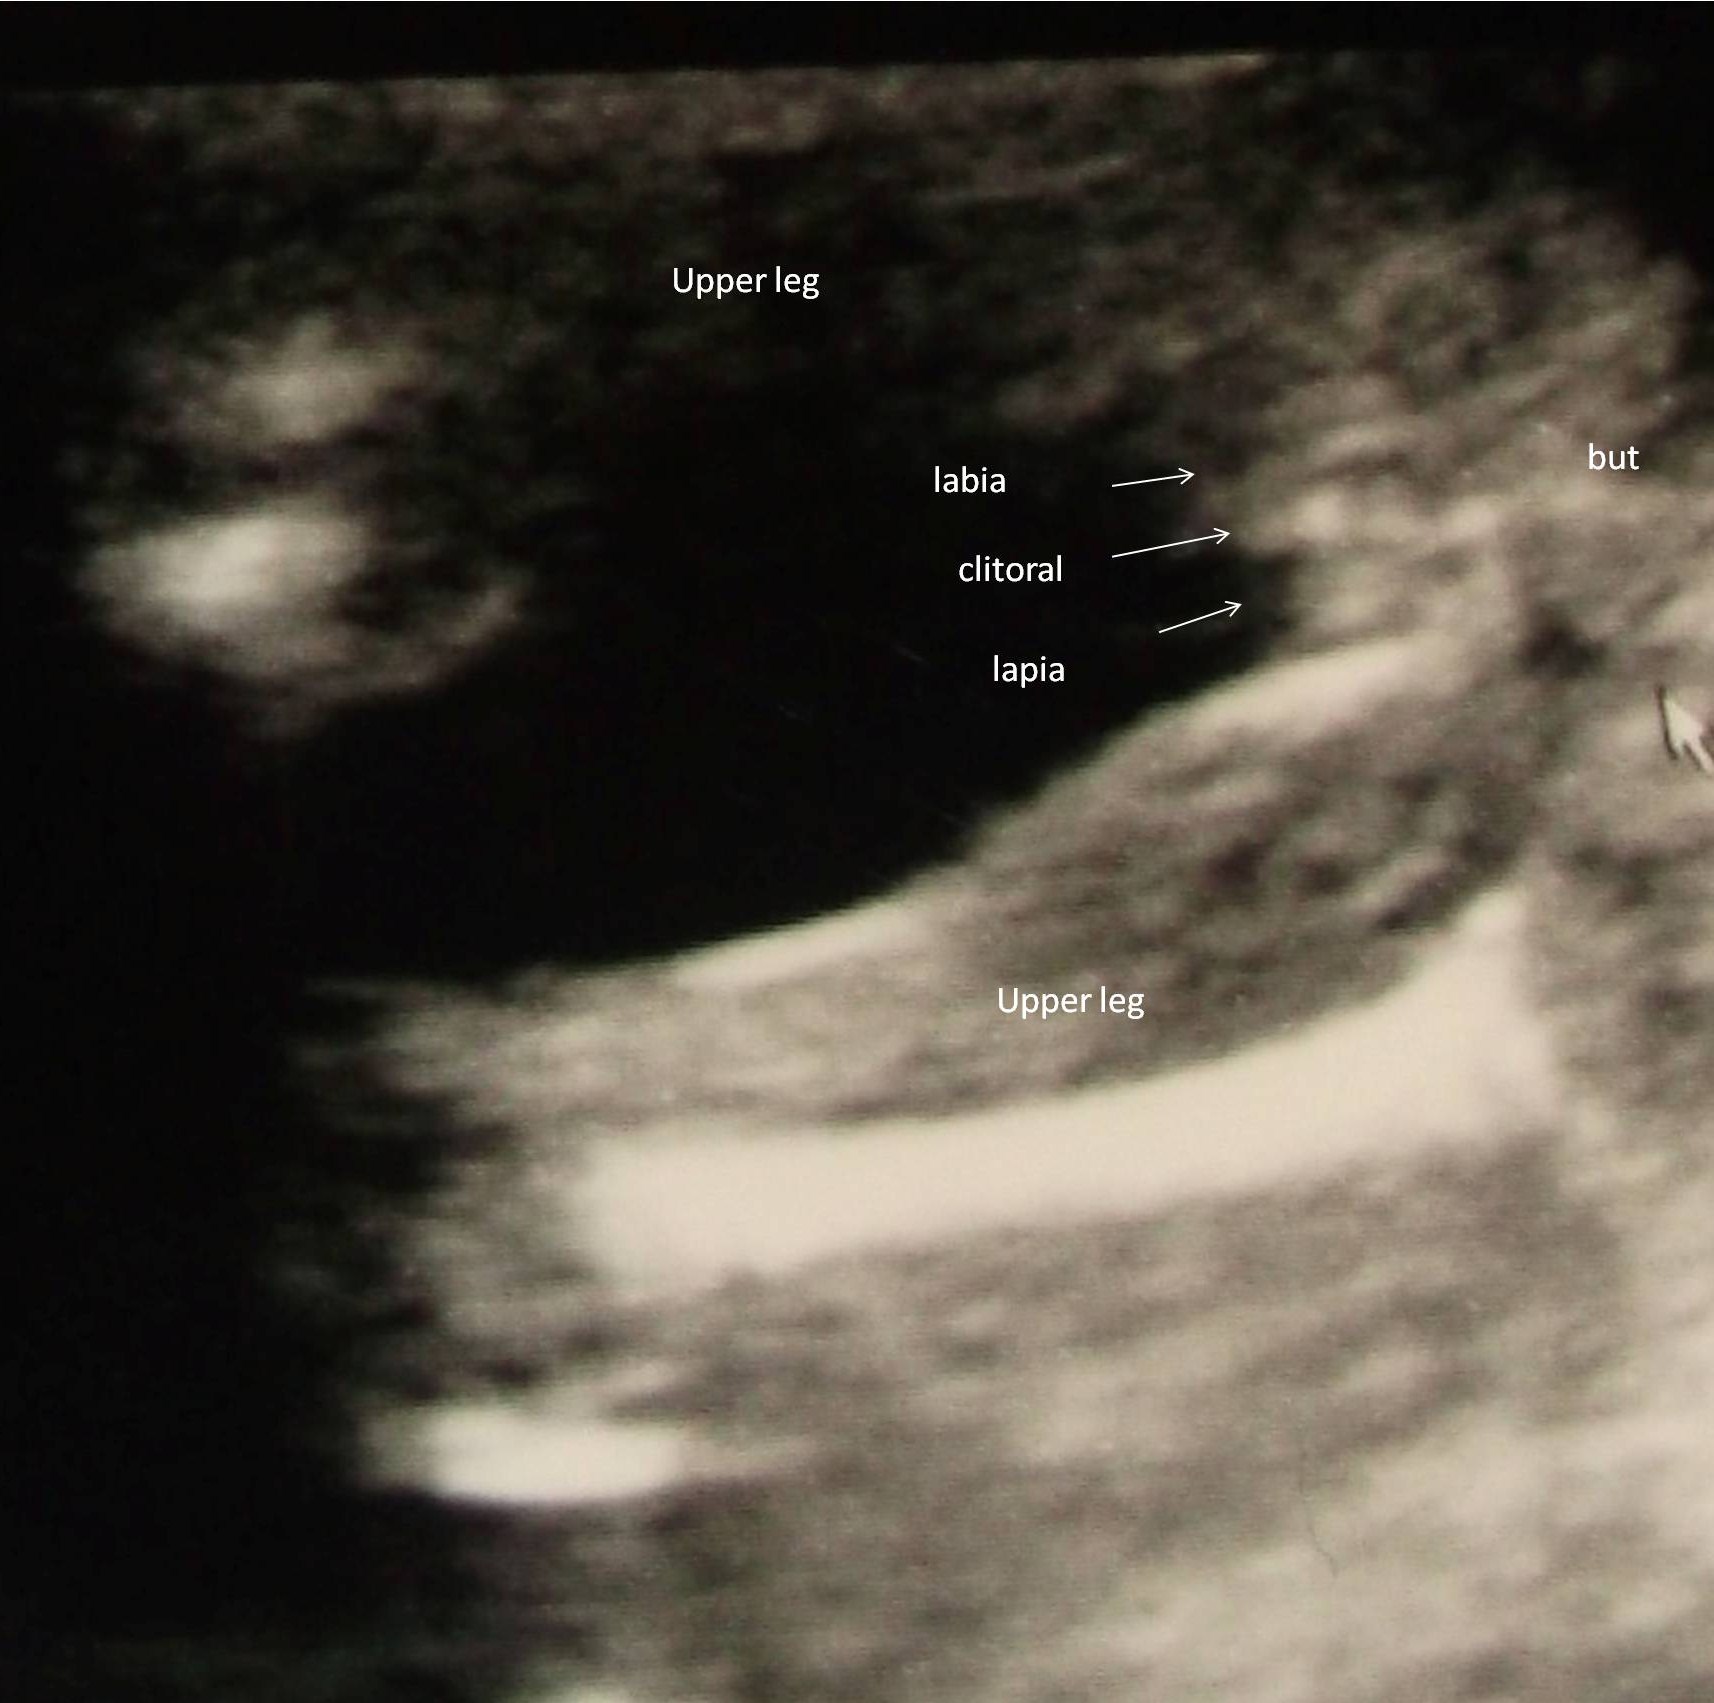

As I had my Organscreen and the doctor said 100% Girl but could not give me a picture

I paid for an Gender Ultrasound today because it made me nervous not to have a Pic.

I saw the Girl parts on the Monitor it was so touching , but to print out a picture was forgotten again :-D so he started again and made this picture witch I don’t find as good as that what I saw on the monitor! Anyway it seems so to be a Girl :-D The doctor said that some boys have “displaced elevation testis” and that this is the only possibility if it’s not a Boy!

So ladies can I tell my family on eastern that we are having a Girl and should I start buying Piiink ???? :-D